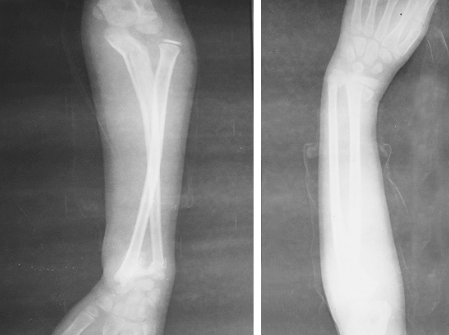

影像学检查:拍摄前臂全长X线片(图2),左尺骨近端骨折,向外成角移位,桡骨小头向外明显移位;尺、桡远端骨折,骨折波及骨骺线,远折块一致性向桡背侧移位,桡骨远折端向近侧压缩移位明显,尺、桡骨远端间隙增大。

图2 伤后6小时X线片